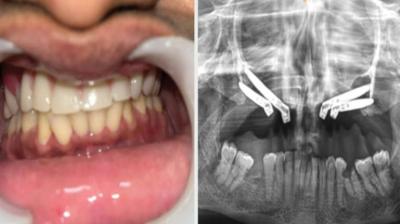

24 वर्षीय युवती के चेहरे पर लौटी मुस्कान और आत्मविश्वास

6 Sep, 2025 10:00 PM IST | R18NEWS.IN

एम्म में जटिल सर्जरी को सफलतापूर्वक अंजाम दिया है। इस सर्जरी में ट्यूमर के कारण काटे गए निचले जबड़े को पैर की हड्डी से दोबारा बनाया गया और उसमें 13...